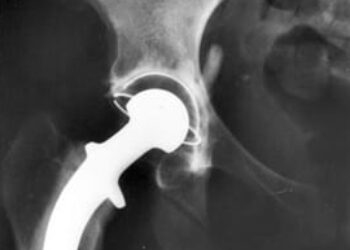

Image: PD